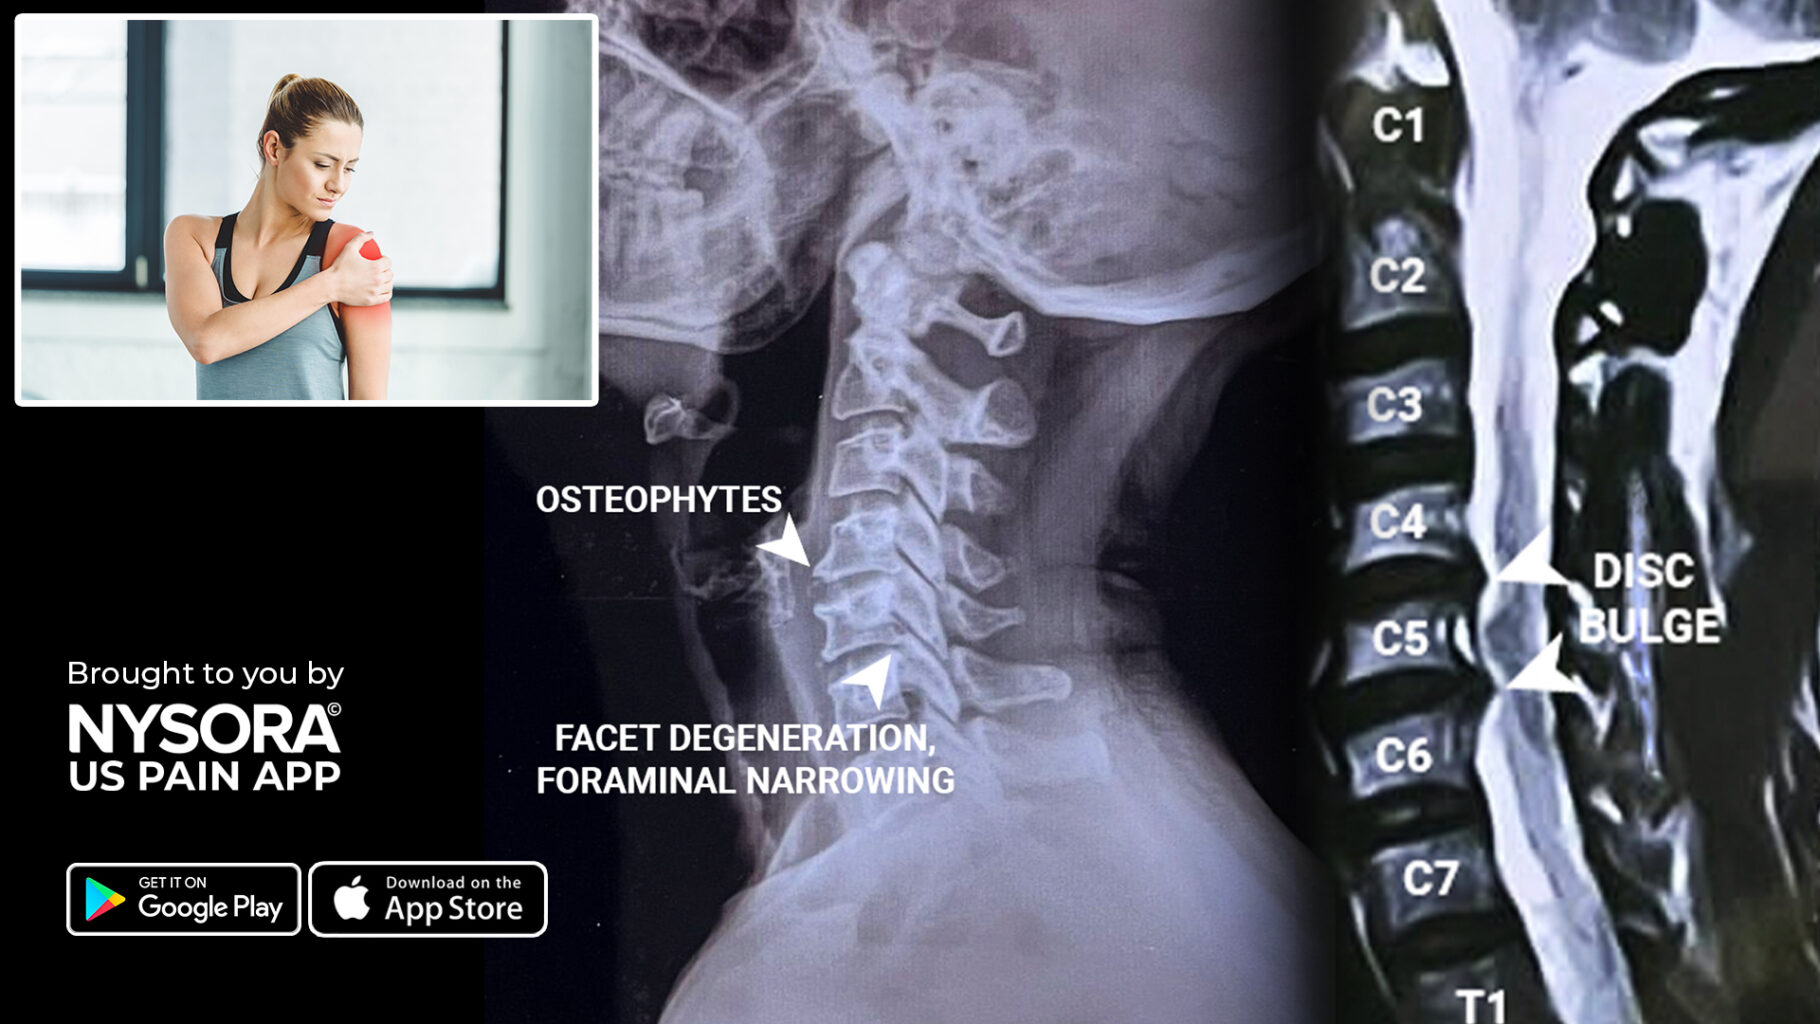

From www.nysora.com

Case study Cervical radiculopathy Injection NYSORA Ibuprofen Dosage For Cervical Radiculopathy Common nsaids used to treat back and neck pain. Cervical radiculopathy describes pain in one or both of the upper extremities, often in the setting of neck pain, secondary to compression or irritation of nerve roots in the cervical spine. Some providers use a methylprednisolone dose pack (tapers from 24 to 0 mg over 7 days); Examples could include aspirin,. Ibuprofen Dosage For Cervical Radiculopathy.